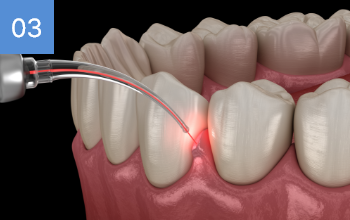

해당환자 치과공포증이 있으셨으나 본원 수면치료 병행하여 편안한

수술 진행되어 만족하심